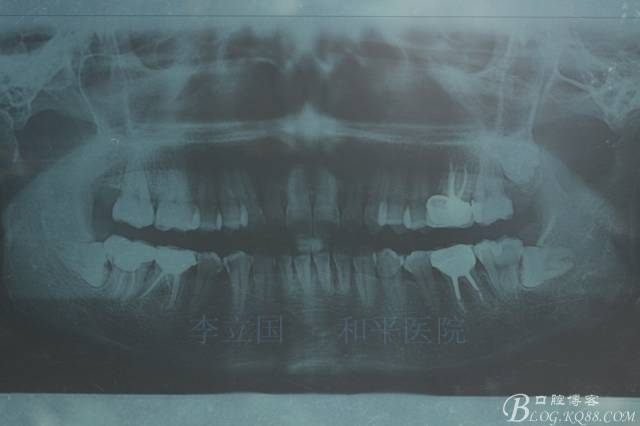

1.拔除14、24、31。

1.患者上前牙直立,面型前突,典型的嘴凸牙不吐,關(guān)鍵是前牙轉(zhuǎn)矩控制,建議使用高轉(zhuǎn)矩托槽。

2.磨牙關(guān)系一側(cè)完全遠(yuǎn)中,一側(cè)遠(yuǎn)中尖対尖,采用兩個(gè)上4,一個(gè)下1的拔牙模式。

3.上頜應(yīng)用支抗釘。表麻下在56牙槽間隔植入,注意因使用的為鈦合金釘,一直保持植入角度與骨面成60度角,不要垂直植入再改變角度。要求即刻加載,即刻加載力值2盎司。